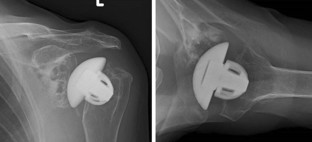

Fig. 1

Fig. 2

Fig. 3

Fig. 4

Fig. 5

Fig. 6